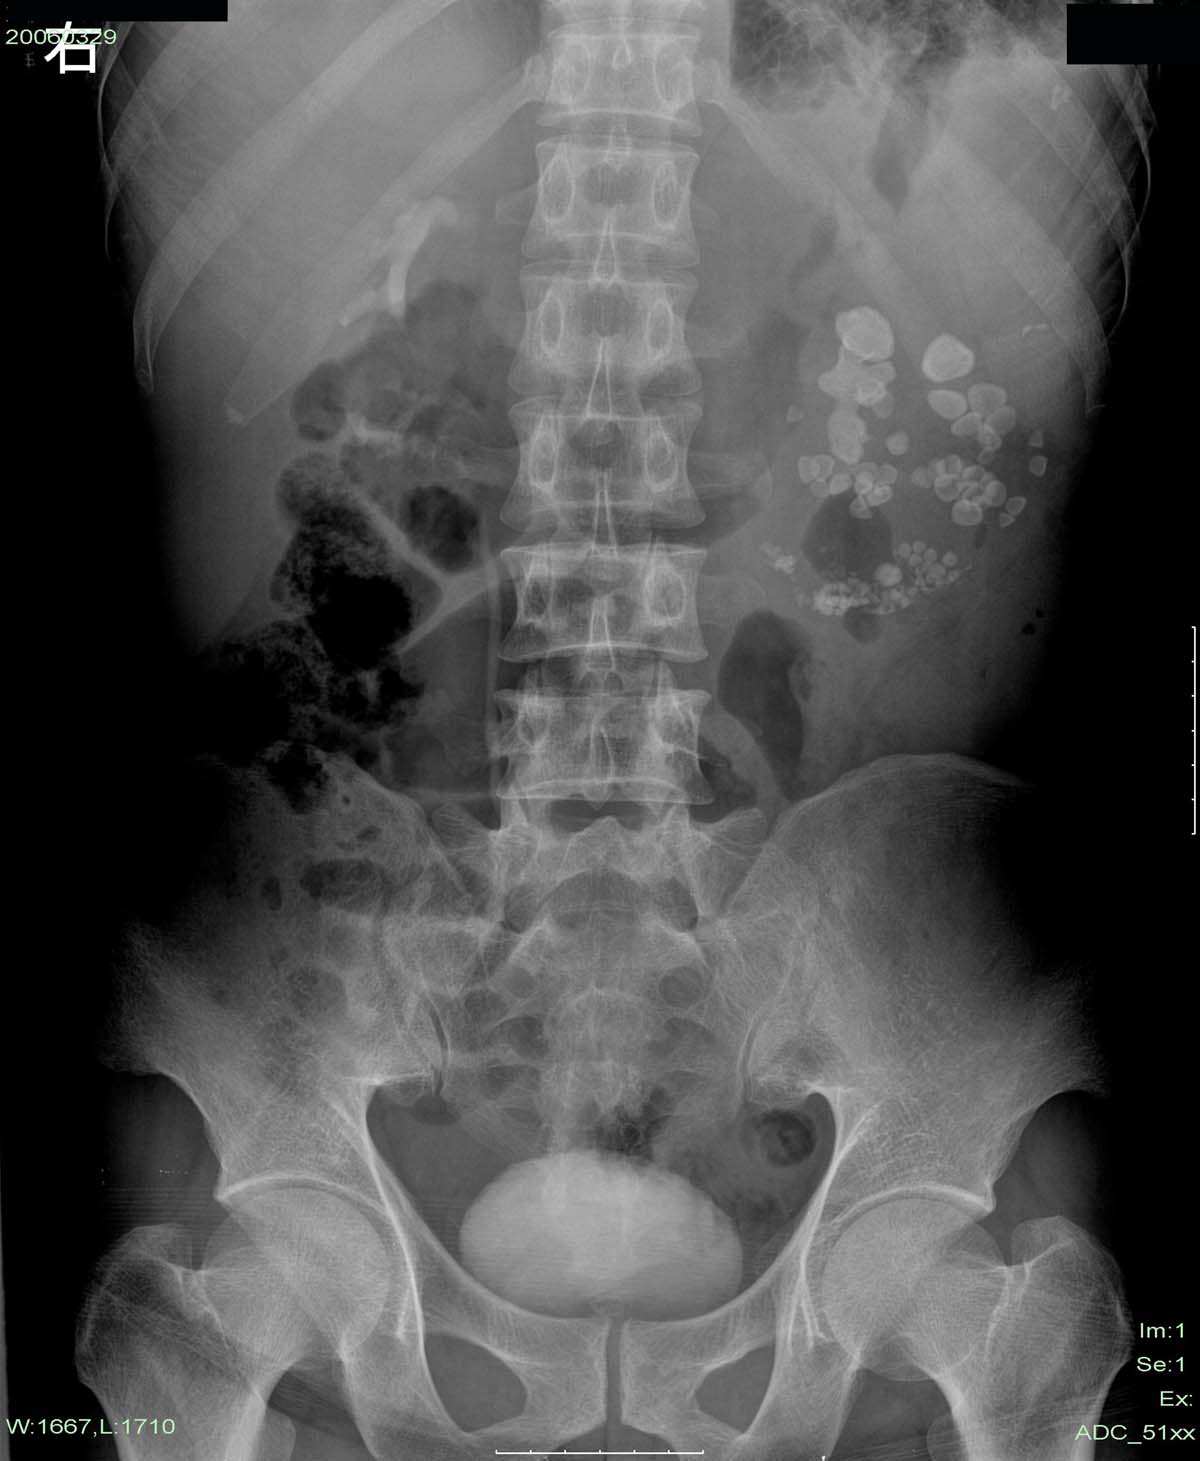

下午做的检查,第二天早上透视,左肾区仍未见造影剂显影。

这个是左肾多发性结石伴重度积水。其与肾自截不同的是:肾自截呈全肾钙化,肾脏缩小.本例肾内密度增高影呈颗粒状,肾影增大.故不支持肾自截

本例造影过程中结石位置,大小等都未有明显改变。左肾体积明显增大,与肾自截相反。且无钙化。故支持向医生的观点。

左肾上极见“鹿角”样结石并中下极多发性结石。左肾重度积水,在该片只是推理而已,左肾没有看到肾盂、肾盏显影。从结石分布看,可以肯定不是肾自截钙化。

1:左肾多发结石,伴重度积水

2:肺部疾患,建议胸片进一步检查